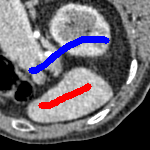

The motivation for this work comes from observing contradictions in using piecewise-constant intensity fitting terms in selective segmentation. Whilst good results are possible with this approach, the exceptional cases lead to severe limitations in practice. This is quite common in medical imaging as demonstrated in Fig. 1, where the target foreground has a low intensity. Given that the corresponding background includes large regions of low intensity, the optimal average intensities for this segmentation problem are and . For cases where , we see that by (1), almost everywhere in the domain . This means that it is very difficult to achieve an adequate result, without an over-reliance on the user input or parameter selection.

for and as defined in (33). This is consistent with respect to the intensities of the observed object and the concept of selective segmentation. In Fig. 3 we see the difference between CV and the proposed fitting terms for given user input on a CT image. For the CT image, the CV fitting terms are near 0 within the target region. This is despite there being a distinct homogeneous area with good contrast on the boundary. This illustrates the problem we are aiming to overcome. With the proposed fitting term this phenomenon should be avoided in cases like this. By defining as in (33) there is no contradiction if the foreground and background intensities of the target region are similar.